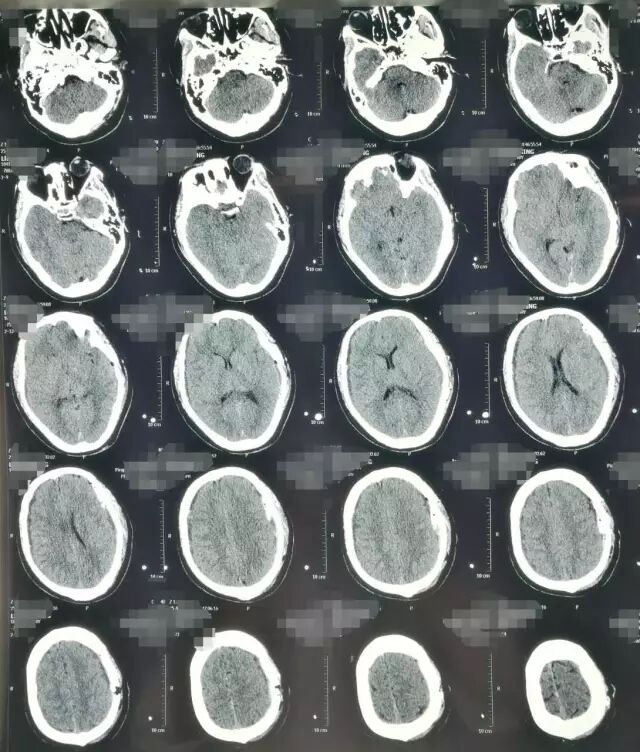

患者,男,40岁;因不明原因反复头痛并加重2月,于2017年4月21日当地医院头颅CT、MRI提示:双侧额颞顶部慢性硬膜下血肿收住院(图1)。并于4月24日行“左侧慢性硬膜下血肿钻孔引流术”。术后患者卧床、静脉补液,头痛症状有所缓解。复查头颅CT显示左侧血肿较前减少,但右侧稍增大(图2)。

图1. 第一次术前CT及MRI显示双侧慢性硬膜下血肿,中线稍右偏。

图2. 左侧慢性硬膜下血肿钻孔引流术后1天复查头颅CT,显示左侧硬膜下血肿较术前减少。